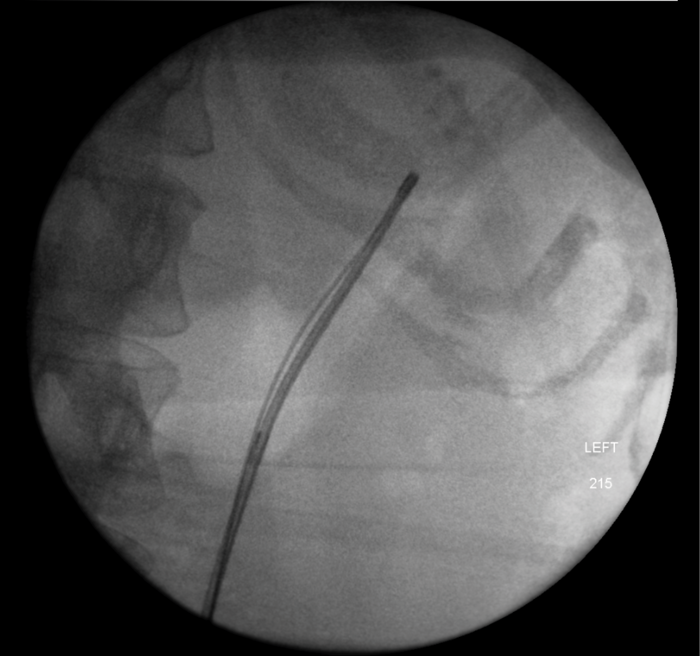

An 80-year-old woman presented with urosepsis requiring direct admission to intensive care. A CT scan demonstrated gas in the collecting system and a nephrostomy was inserted.

Figure 2: Nephrostogram showing stone in left kidney with nephrostomy in place prior to flexible ureteroscopy.

The patient made a good recovery from her life-threatening sepsis, retaining function on a DMSA scan and underwent a flexible ureteroscopy to clear the stone. Gas forming organisms in the urinary tract result in dramatic imaging but should not distract from the patient’s clinical condition. A conservative approach may avoid a nightmare nephrectomy in a highly morbid patient.